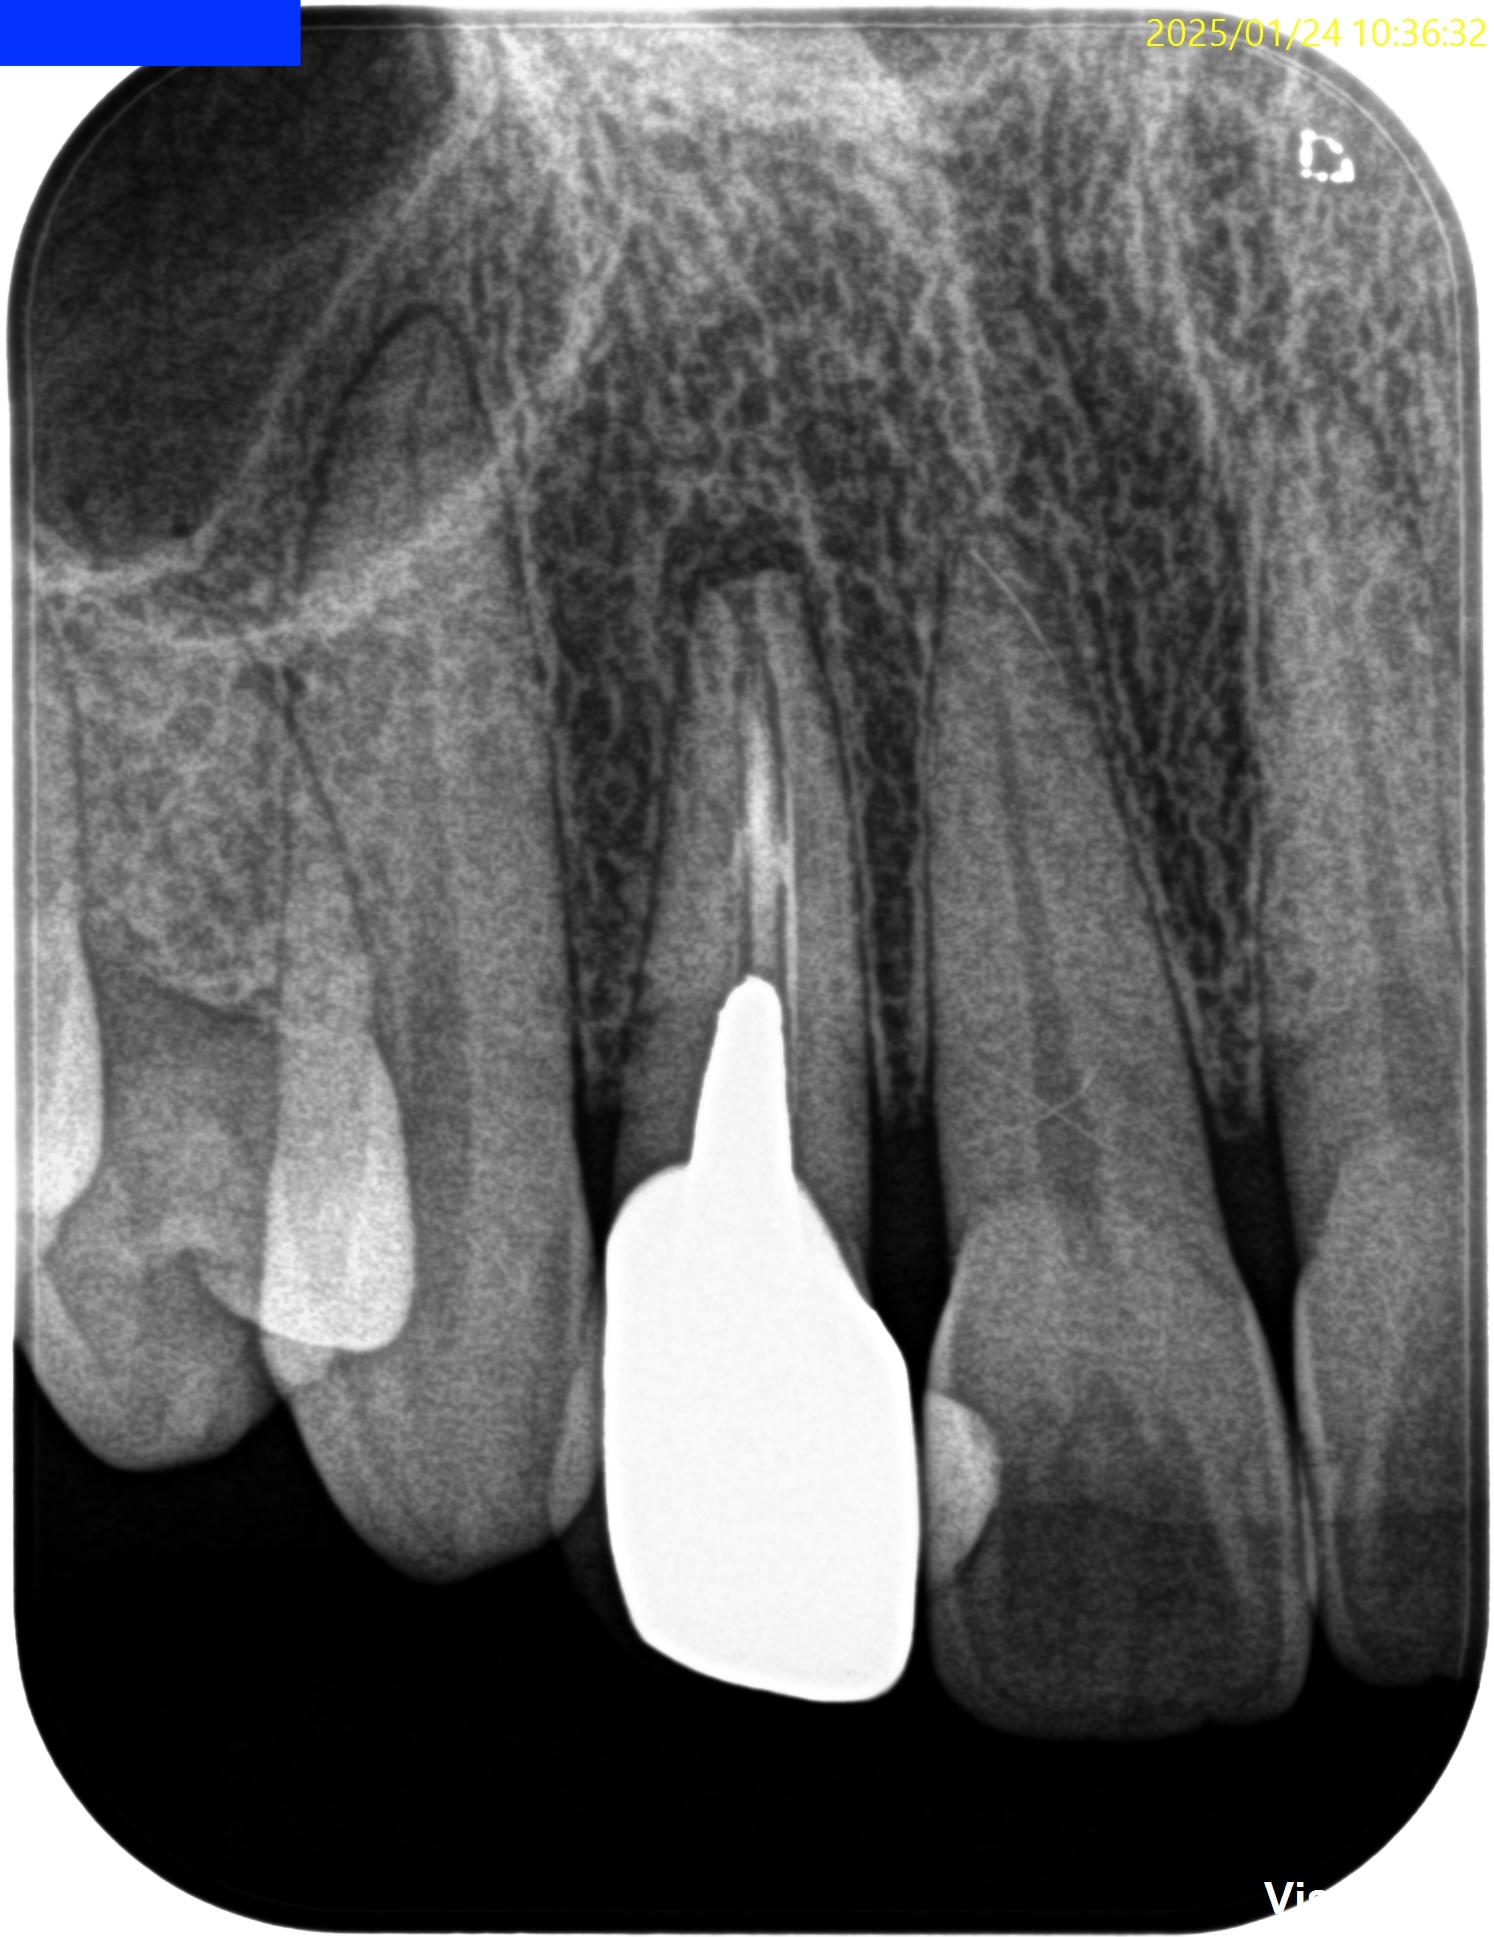

Pre-op Endo test(2025.1.24)

初診時は症状がなかったがかかりつけ医では打診痛があったようだ。

根尖が既に開いており、圧痛があったことから治療は再根管治療ではなく、歯根端切除術であるということがわかる。

Pulp Dx: Previously treated

Periapical Dx: Asymptomatic apical periodontitis

Recommended Tx: Core build up w Fiber Post⇨Apicoectomy